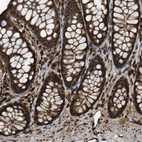

Immunohistochemical staining of human prostate shows strong nuclear and cytoplasmic positivity in glandular cells.